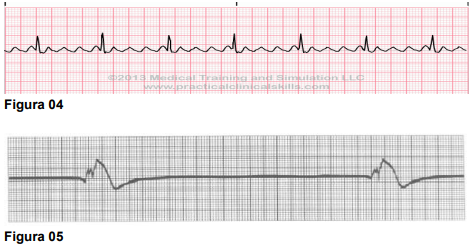

A atuação do enfermeiro na monitorização cardíaca exige não apenas habilidade técnica, mas também sólido embasamento teórico. A avaliação clínica fundamentada nos sinais vitais, especialmente nos ritmos cardíacos, é indispensável para uma assistência eficaz e segura. Nesse contexto, o conhecimento das

arritmias cardíacas assume papel crucial nos diversos níveis de atenção, uma

vez que permite a identificação precoce de situações de risco iminente e favorece a tomada de decisões assertivas em conjunto com a equipe multiprofissional, promovendo, assim, uma assistência integral à saúde.

A seguir, apresentam-se cinco traçados cardíacos que devem ser analisados quanto à sua morfologia e frequência, a fim de identificar corretamente o tipo de arritmia associado a cada um, respectivamente.

Assinale a opção CORRETA, referente à sequência das arritmias apresentadas: